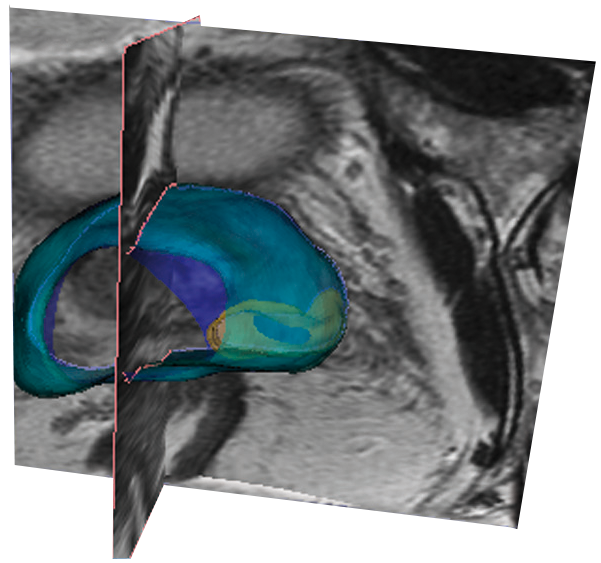

Dans plus de 80% des cas on peut voir par l’IRM un tissu suspect de cancer. Et ça change tout. Dès qu’on a le moindre doute, avec un PSA un peu élevé ou un toucher rectal anormal, on va faire une IRM. C’est devenu l’examen clé. Maintenant, l’IRM sert à guider les biopsies. C’est une révolution purement technologique qui a servi à pouvoir déceler le cancer.